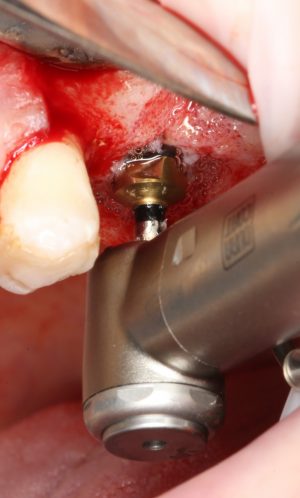

Приступаем к установке имплантата.

Кстати, комплект поставки не содержит ни заглушки, ни абатмента. А сам имплантат фиксируется на ключе простым заклиниванием платформы. Т. е. не слишком надёжно:

По этому поводу существует поговорка: «Кто не ронял имплантаты Astra Tech, тот не работал с имплантатами Astra Tech«. В общем, будьте аккуратны, в идеале, проводите все манипуляции по фиксации имплантата на ключе над столом.

Если лунка подготовлена правильно, то имплантат проваливается в неё почти полностью:

и докручивается до правильного положения несколькими оборотами.